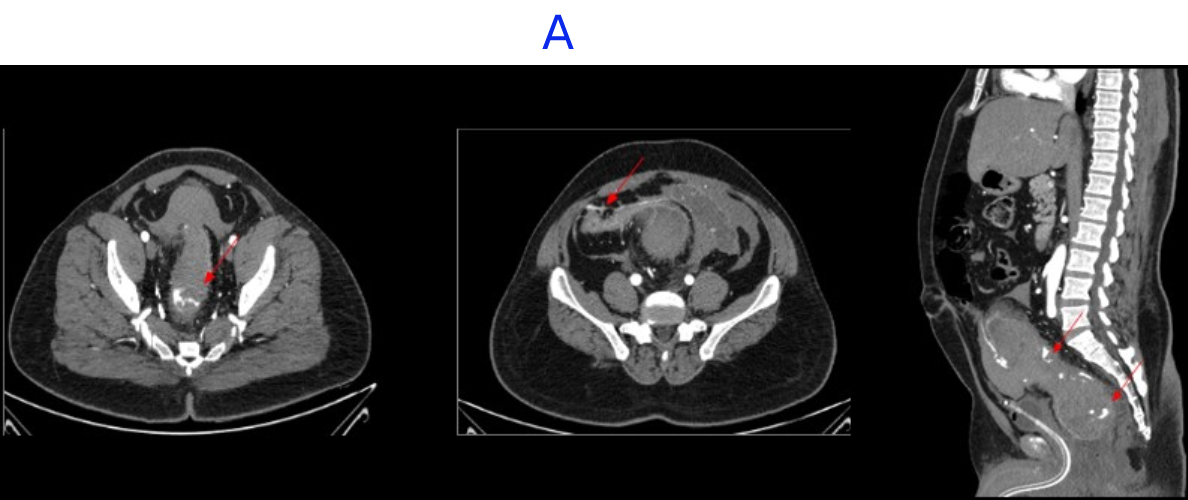

A. LEGENDS

- Large intramural hematoma with significant adjacnet fat starnding noted in rectum and distal sigmoid causing significant luminal narrowing.

- Multiple area of contrast extravasation within the hematoma which shows increase in size in venous and delayed phases with multiple pools of contrast - suggesting active bleeding from branches of inferior mesenteric artery..

- Distal rectum and proximal sigmoid colon mild edematous wall thickening.

- Hemorrhagic fluid noted in bilateral paracolic gutter and pelvis with active contrast extravasation.

- Omentomesenteric fat stranding in lower abdomen with mesorectal fascial thickening noted.